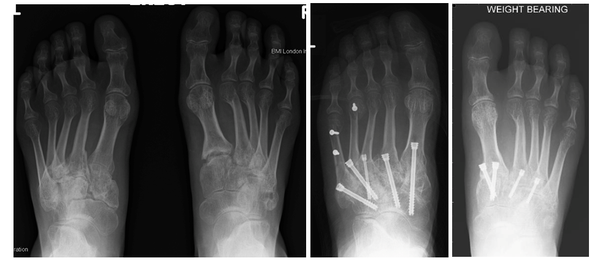

A car crash has resulted in extensive fractures and poor alignment of the midfoot, with the left side worse than the right. The left foot has subsequently undergone a fusion of all the midfoot articulations (eight joints), whereas the injury on the right was less extensive and just three joints were fused, with less stiffness and better function as a result.